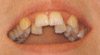

Distalbiss

Der Rückbiss (Prognatie oder Retrogenie) oder Distalbiss entsteht

häufig durch Zahnengstand im Oberkiefer. Er ist im Vergleich zum

Unterkiefer zu lang, so daß die oberen Schneidezähne nach vorne

verlagert sind, oder der Unterkiefer ist zu kurz. Somit tritt eine

gut sichtbare Disharmonie beim Zusammenbiß zwischen Ober- und Unterkiefer

ein,was sich ungünstig auf das Gesichtsprofil auswirkt.